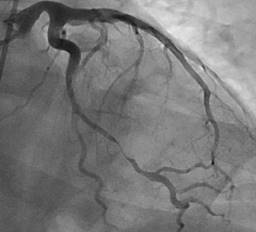

Medical treatment was started with a single 300 mg loading dose of acetylsalicylic acid and, subsequently, 100 mg every 24 hours, a single 600 mg loading dose of clopidogrel, a single 40 mg loading dose of subcutaneous nadroparin every 24 hours, single 80 mg dose of atorvastatin and subsequently 40 mg every 24 hours, 50 mg metoprolol every 12 hours and amiodarone infused at 1 mg/min for 6 hours and subsequently at 0.5 mg/min due to the arrest rhythm presented. Coronary angiography was performed, showing type 2a spontaneous coronary dissection of the distal third of the circumflex artery, the second obtuse marginal artery (OM2) with TIMI 3 residual flow and extensive intramural hematoma (IMH) (Figure 2). His care was continued in the special care unit, where he remained stable and had no recurrence of arrhythmias. A control electrocardiogram was taken that showed the resolution of the electrocardiographic alterations (Figure 3). Transthoracic echocardiography reported a slightly reduced ejection fraction (50%) and akinesia with the remodeling of the basal segment of the inferior wall, without other relevant findings. Magnetic resonance angiography of abdominal vessels was performed without evidence of changes in intra-abdominal visceral arteries for fibromuscular dysplasia.

Figure 2: Type 2a spontaneous coronary dissection of the distal third of the circumflex artery and the second obtuse marginal artery. Source: Own creation.

There is no clarity on which patients should be provided with medical management; however, it has been proposed that candidates should have a TIMI flow > two and hemodynamic stability with hospital surveillance between 5-7 days, since the extension of the intramural hematoma, or IMH, can occur in the 5-10% of cases.21 In our case, we present a type 2a SCAD of the distal third of the circumflex artery and the second obtuse marginal artery (OM2) that generates long tubular stenosis, in some segments of 90%, with residual TIMI three flow and extensive intramural hematoma. Our report agrees with that found in the literature, where the main precipitant in men is physical activity, with studies showing a presentation of 44% vs 2.8% in women.11